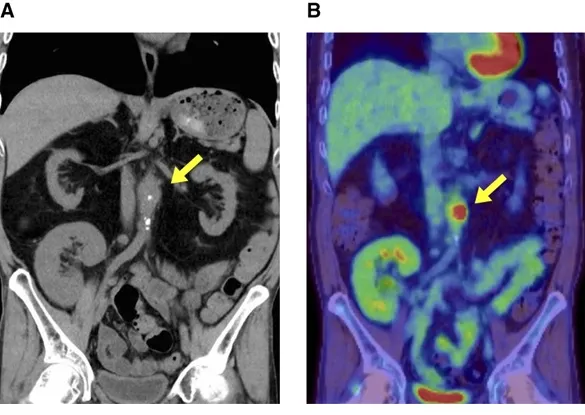

Aortite em um transplantado renal: raro, mas com implicações importantes